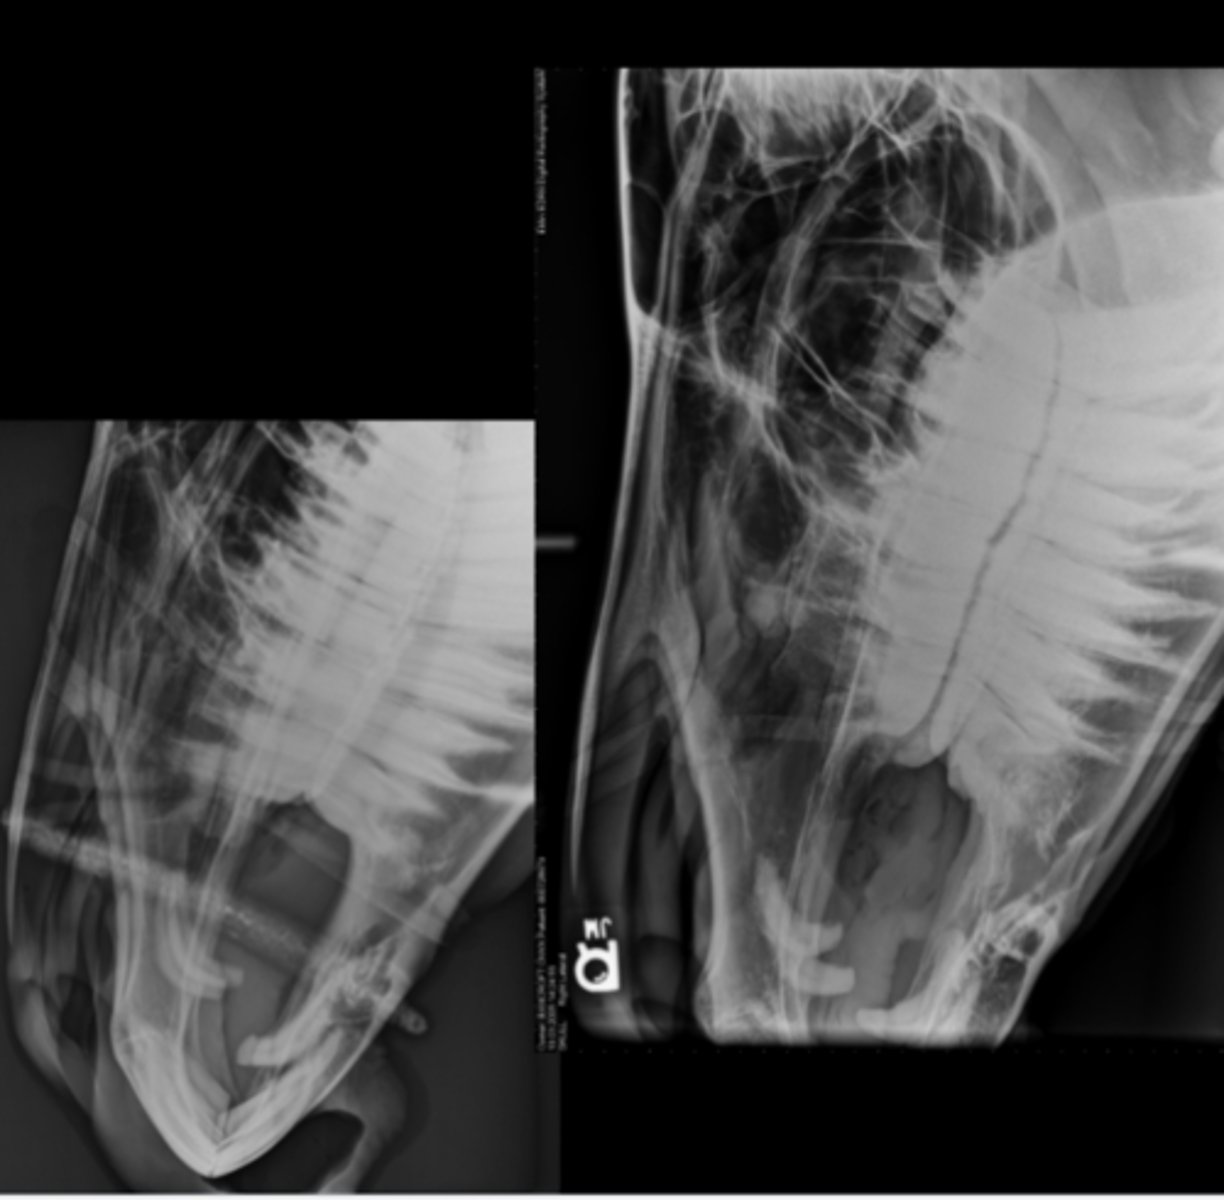

Equine Skull

LG Animal Skull - DV image

• Tube dorsal, plate ventral

• Marker to indicate laterality

LG Animal Skull - Lateral image

• Tube on one side, plate on the other

• Marker to indicate laterality closest to plate

LG Animal Skull - DV Oblique image

• Tube angled in DV plane, plate held perpendicular

• Markers indicate anatomy that is closest

• Maxillary or mandibular structures